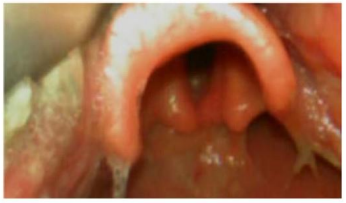

Ao proceder à laringoscopia direta, o plantonista deparou com a via aérea demonstrada na imagem. Diante disso, assinale a alternativa que corresponde à melhor conduta para o caso.

O plantonista, ao decidir pela intubação, teria como melhor opção mais assertiva, na sequência rápida de intubação, os medicamentos